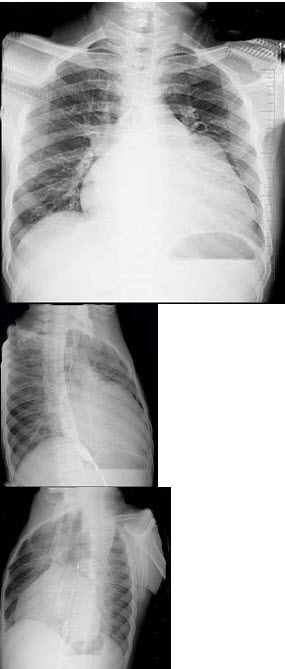

女,21岁,反复关节红肿疼痛5年,活动后心悸气促1天入院。查:梨形心界,心率88次/分,律齐,心尖区舒张期隆隆样杂音,P亢进;Hb88g/L;胸片结果如图所示。

可诊断为()

A:左房粘液瘤

B:贫血

C:风心病、二尖瓣狭窄

D:冠心病

E:Austin-Flint杂音

56岁男性患者,劳累后心慌气促10余年,近来自觉症状加重。临床听诊,心尖区有舒张期隆隆样杂音,行胸部X检查,如图所示,你认为下列描述正确的是( )

A:后前位示双侧肺血增多,肺动脉段隆起,左心缘出现第3弓

B:右前斜位示左心房增大,心后上缘后突压迫冲钡食管

C:左前斜位示心影向后下方突出

D:考虑三尖瓣狭窄

E:考虑二尖瓣狭窄